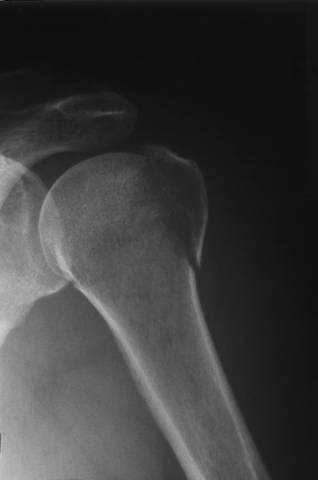

Kuva 1.

Humeruksen kaulan ja tuberculum majuksen murtuma.

Diafyysin murtuma on hyvässä asennossa ja lähes huomaamaton nivelkapselin ja lihasten tukemana.